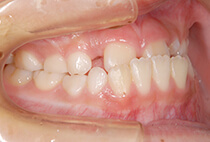

治療前

治療後

しっかり前歯を下げるために、インプラントアンカーを使用してコントロールしました。

かみ合わせが整うと咬筋の過緊張が改善。

過緊張による筋肉肥大も改善しフェイスラインもすっきりしました。